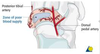

Risk factors for developing this pathology

males (male to female ratio is 3:2)

African Americans

Pacific islanders

obese children - single greatest risk factor

during period of rapid growth

bilateral in 20% (20-40% May go on to develop bilateral)